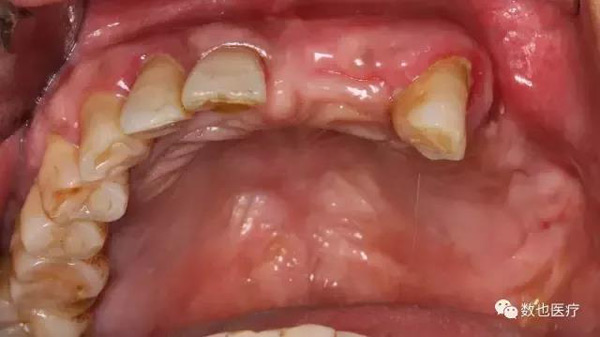

患者口内照